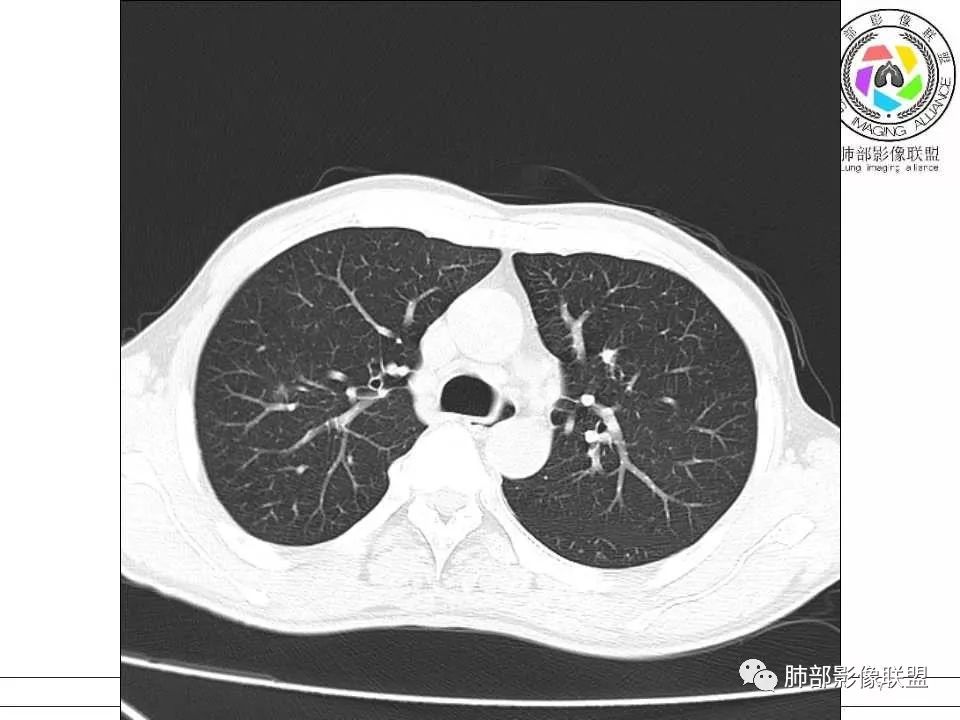

双肺弥漫小树丫,树丫边界清楚,右肺磨玻璃结节,病变包绕血管束,血管走形自然(考虑微浸润腺癌)。左肺下叶多发实性结节,结节以支气管血管束周围分布,大小均一,部分结节伴有空洞,洞壁内侧可见引流支气管及支气管壁增厚,洞壁外侧可见钙化,随访两个月有明显吸收,部分有残留小结节。中老年男性,无实验室检查。考虑:左肺炎性肉芽肿,结核,隐球,组织胞浆菌,NTM,建议完善实验室检查及支气管镜检查。

患者中年男性,咳嗽咳痰两周。胸部CT:右肺上叶尖段不规则混合磨玻璃结节,见分叶、毛刺及血管穿行征象。左肺下叶前基底段沿支气管血管束分布外大内小片状实变、磨玻璃及空洞影,空洞壁薄,见平直、钙化征象。4月多后复查胸部CT,右肺上叶病灶变化不大,左肺下叶病灶明显吸收,遗留部分结节灶。期间治疗方案不详。综合考虑右肺上叶腺癌可能性大(微浸润至浸润),鉴别结核。左下肺炎性病变,结核可能性大,鉴别小细胞癌。

右肺上叶混合性磨玻璃结节,边缘清晰,磨玻璃内可见多发小空泡,五个月后增大。左肺下叶空洞,周围多结节堆积。病灶见引流支气管,周围卫星灶。二元论:右肺上叶浸润性腺癌,左肺下叶结核。

右肺上叶混合磨玻璃结节,有分叶毛刺,复查有增大,高密度有增多,考虑肺腺癌。左肺下叶病灶,内见空洞且空洞内壁光滑,周围见花花草草,复查部分病灶有吸收,考虑炎性病变,结核? 医学百科网 | YxBaike.Com

中年男性,咳嗽咳痰2周。CT:1.左下肺主病灶近圆形结节,内见空洞、钙化,周围索条、实变影,5个月后主病灶没有明显变化,周围病灶似有减少,考虑陈旧性病变;2.右上肺混合磨玻璃结节,见移动联通血管,边缘磨玻璃影边缘清楚,5个月后结节增大,考虑恶性肿瘤——IAC。 医学百科网 | YxBaike.Com

中年男性,咳嗽、咳痰2周。CT:1.左下肺主病灶类圆形结节,内见空洞,有引流支气管,周围索条、实变影,4个月后主病灶没有明显变化,周围病灶变化不大,考虑慢性炎性病变,TB?2.右上肺mGGN,实性成分不规则,血管进入,病灶边缘清楚,4个月后结节增大。考虑:腺癌,MIA? 医学百科网 | YxBaike.Com

右上叶磨玻璃结节,边清,分叶,5个月进展,似有变大,实性成分增加。左下肺内前底段结节及周围渗出,内有钙化,5个月吸收缩小。意见:右肺IAC,左肺TB。

毛勤香: 医学百科网 | YxBaike.Com

右肺上叶混合磨玻璃结节,边缘清晰,分叶,血管进入稍增粗,隐约小空泡,约5月复查密度稍增高,考虑LPA;左肺下叶结节,新月形厚壁空洞,引流支气管稍增粗,钙化,周围树芽征,复查病灶变小,考虑结核。

中年男性。第一次CT右肺上叶后段mGGN,边缘GGO边界清楚,其内血管影杂乱扭曲。左肺下叶前内基底段结节,边界清楚,其内见粗糙钙化,近肺门侧见空洞,似与近端支气管相通,并支气管壁似有增厚,周围见卫星灶、树芽征、纤维条索及胸膜牵拉征,临近叶间胸膜轻度增厚牵拉移位。4个多月后复查,右肺上叶结节实性成分似有增多,病灶似有增大。左肺下叶病灶明显缩小。考虑右肺上叶后段肺癌,腺癌可能性大(MIA或IAC);左肺下叶前内基底段结核。

右肺上叶磨玻璃结节,边界清晰,内可见血管穿行,复查后病灶明显增大,实性成分增多,考虑腺癌。另左肺下叶病灶,内可见空洞伴钙化,周围可见散在卫星灶及索条,复查后病灶缩小,考虑结核。

右肺上叶后段混合磨玻璃结节,边界清晰,短毛刺、分叶,小叶阻挡,其内血管增粗、迂曲,考虑腺癌(IAC)。左肺下叶前基底段结节,可见厚壁空洞,内壁光整,可见引流支气管,壁可见钙化灶,边缘可见长毛刺、胸膜牵拉,周围卫星灶,考虑结核。 医学百科网 | YxBaike.Com

右上肺腺癌,左下肺结核

当肺部有结核或炎性背景时,如果肺部某一区域出现孤立性的GGO结节或实性结节的时候,一定要警惕:一是需要仔细分析孤立性GGO或实性结节的影像特征,看结节边界GGO是否清楚?周围是否有卫星灶等?结节内血管改变?是否有增粗或结构扭曲?是否有空泡征,胸膜凹陷?结节收缩力?毛刺分叶征等等。二是必要时结合治疗后复查,对照结节的大小,密度,形态等改变再一步分析。三是需要按肺部结节指南进行随访。一定不能忽视! 医学百科网 | YxBaike.Com